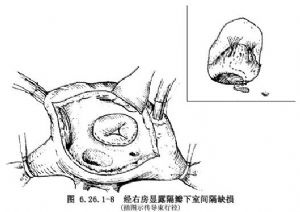

③隔瓣下缺損修補方法:隔瓣下缺損又稱房室管型室間隔缺損,該部位缺損常被三尖瓣隔瓣掩蓋。於三尖瓣隔瓣置2根牽引線,牽開三尖瓣隔瓣多可顯露其下方缺損。假如掩蓋室間隔缺損的瓣葉或腱索無法牽開,可於三尖瓣隔瓣根部距瓣環2~3mm處切開三尖瓣,並將切開瓣葉牽往前方,隔瓣下方缺損即得到良好顯露(圖6.26.1-8)。三尖瓣隔瓣直接與缺損相鄰,頭、尾側分別爲鬥隔和小梁隔,以及右室流入道間隔。頭側三尖瓣隔瓣裂常指向中央纖維體,三尖瓣下方室間隔缺損後下緣有傳導束經過,穿越中央纖維體後分爲左右束支,左束支在室間隔左室面內膜下行走,右束支在室間隔膜部下方分出後,於右室面心內膜下向前進入調節束抵達前乳頭肌基部。圖6.26.1-8插圖顯示了冠狀靜脈竇、房室結,房室束和束支走行與室間隔缺損關係。應用帶墊片和褥式縫線於缺損後下緣做5~6間斷褥式縫合,鄰近三尖瓣環處的縫線縫於三尖隔瓣根部,其他部位縫線緣縫於室間隔的右室側,以免損傷傳導束。上述縫線分別穿過補片相應邊緣並結紮(圖6.26.1-9A)。然後以5-0無創縫線縫合切開的三尖瓣(圖6.26.1-9B)。然而大多數情況下閉合此類缺損可不需切開三尖瓣葉,僅需牽開三尖瓣隔瓣,顯露和修補隔瓣下缺損(圖6.26.1-10)。